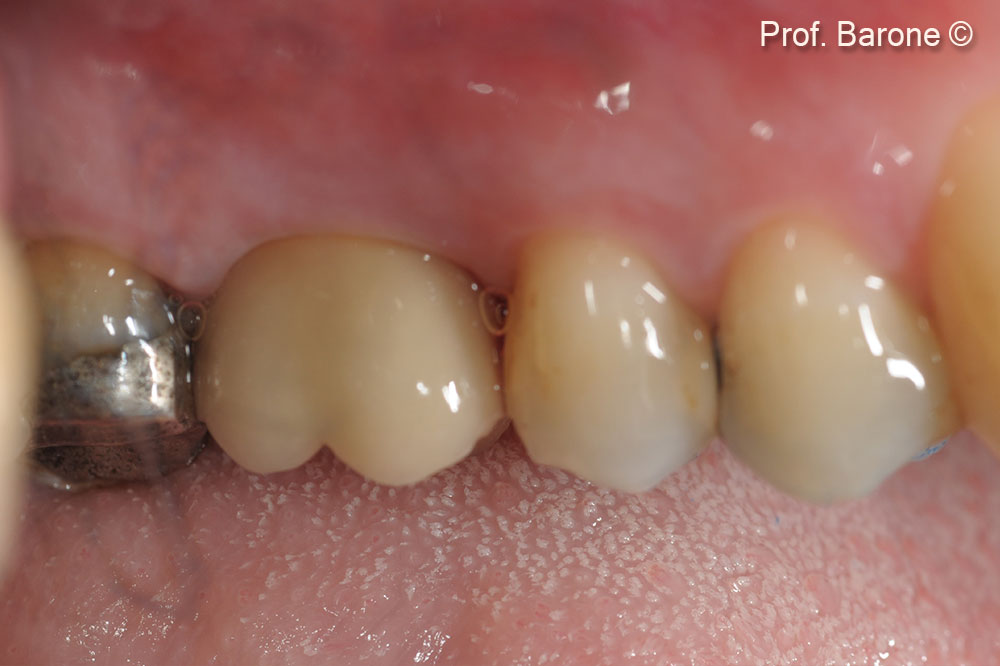

Final Restoration at 3-year follow-up